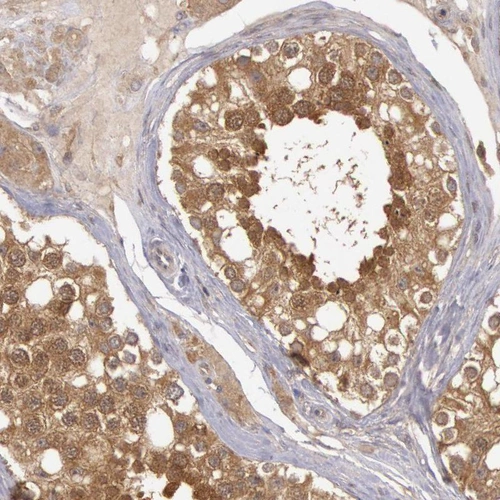

Immunohistochemical staining of human testis shows moderate cytoplasmic positivity in cells in seminiferous ducts.